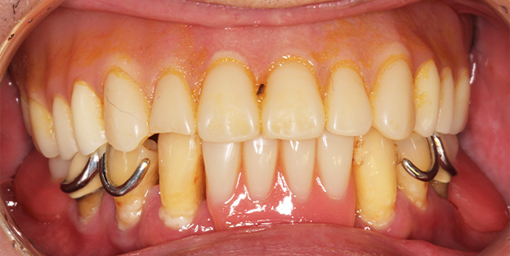

自分の歯を残しながら、噛みやすさと見た目を良くしたい 【オールオン6・義歯】